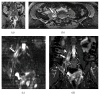

Magnetic resonance neurography is a high-resolution imaging technique that allows evaluating different neurological pathologies in correlation to clinical and the electrophysiological data. The aim of this article is to present a review on the anatomy of the lumbosacral plexus nerves, along with imaging protocols, interpretation pitfalls, and most common pathologies that should be recognized by the radiologist: traumatic, iatrogenic, entrapment, tumoral, infectious, and inflammatory conditions. An extensive series of clinical and imaging cases is presented to illustrate key-points throughout the article.